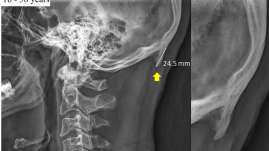

Uso exsesivo de celular crea cuerno en cráneo de usuarios

Cada vez que una persona mira el teléfono celular o cualquier otro dispositivo tecnológico que tenga en sus manos (tablet o mini...